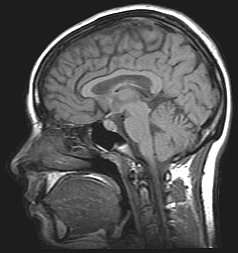

Brain structures

The leading experimental technique for studying proactive interference in the brain is the "recent-probes" task, in which participants must commit a given set of items to memory and they are asked to recall a specific item indicated by a probe.[10] Using the recent-probes task and fMRIs, the brain mechanisms involved in the resolution of proactive interference have been identified as the ventrolateral prefrontal cortex and the left anterior prefrontal cortex.[11]

Retroactive Interference has been localized to the left anterior ventral prefrontal cortex by magnetoencephalography (MEG) studies investigating Retroactive Interference and working memory in elderly adults.[25] The study found that adults 55–67 years of age showed less magnetic activity in their prefrontal cortices than the control group. Executive control mechanisms are located in the frontal cortex and deficits in working memory show changes in the functioning of this brain area.[25]